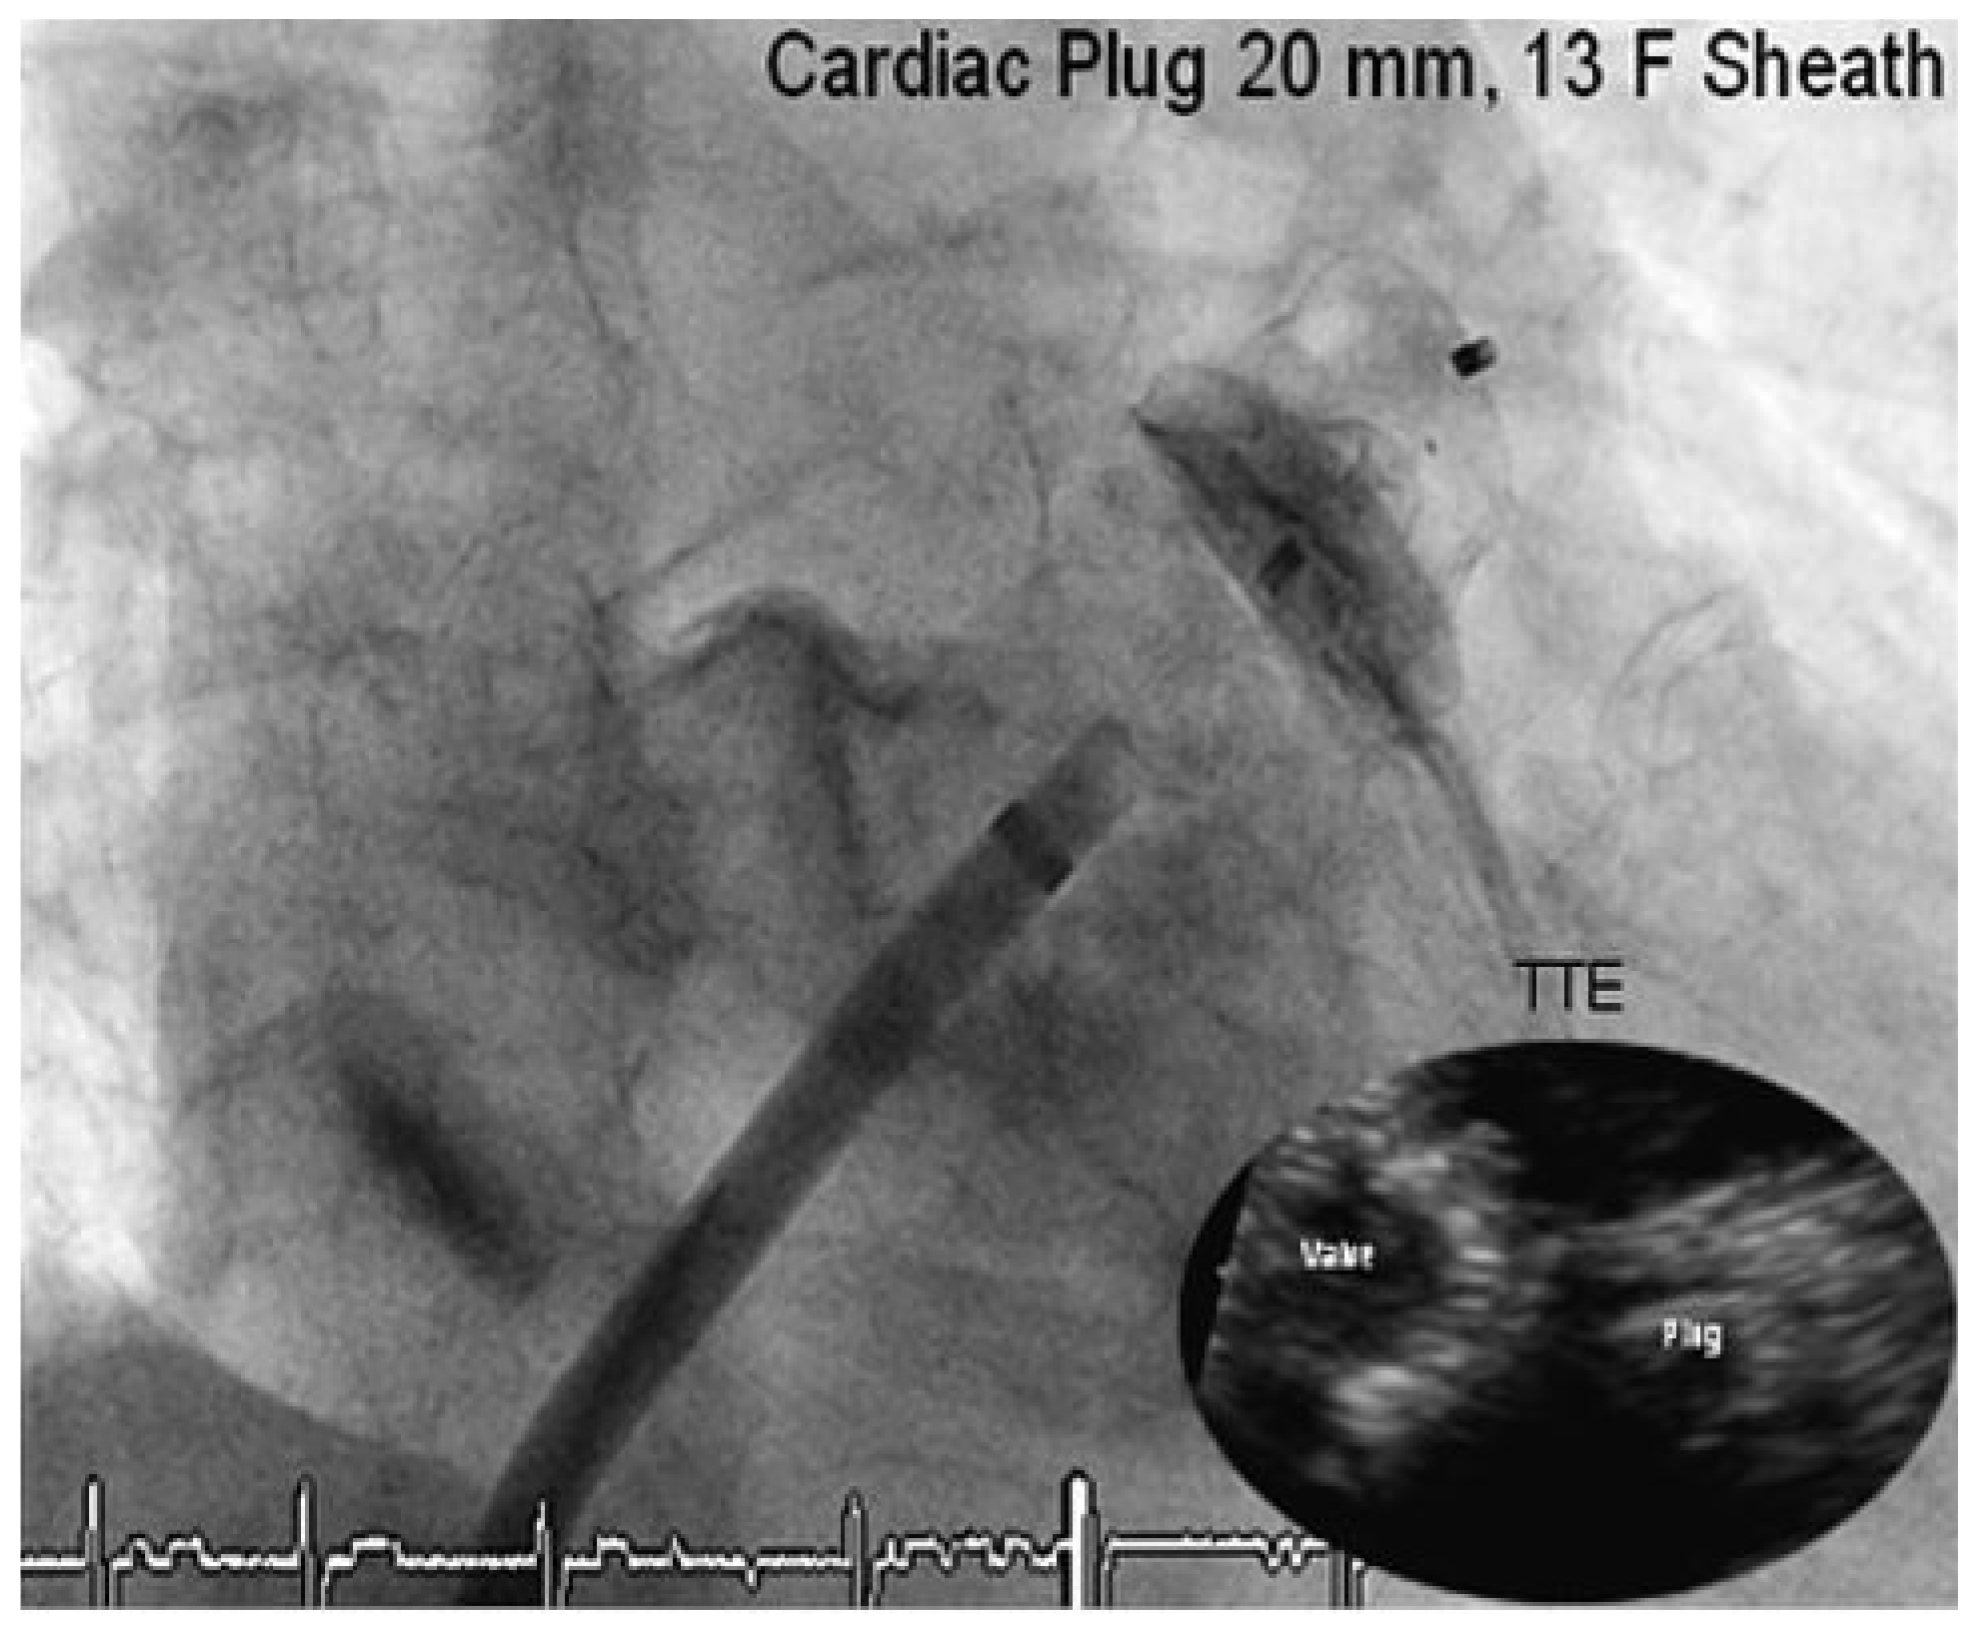

Through a transfemoral venous approach and transseptal puncture, the left atrial appendage was identified and an Amplatzer cardiac Plug 20 mm was positioned in the entry of the appendage. A stable position of the device and complete occlusion of the retroverted, single-lobulated appendage were verified by angiography before the device was released from the catheter (

Figure 1 and

Figure 2). Thereafter, coronary angiography was performed which showed significant stenosis of the mid left anterior descending coronary artery (LAD) and the proximal left circumflex coronary artery (LCX). Following successful treatment with two everolimus-eluting stents, respectively (